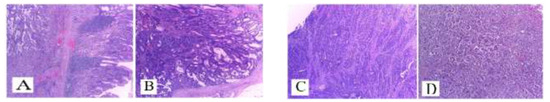

Case presentation